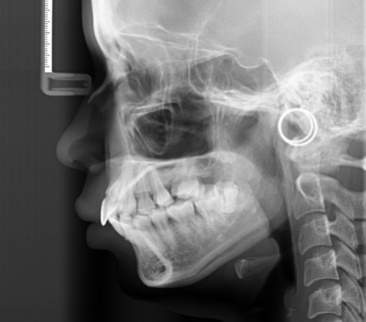

二、頭顱側位片

可以睇到患者上下頜骨嘅關係、牙齒位置同埋軟組織側貌,從而判斷係牙性定係骨性嘅錯頜畸形,預估正畸後對側貌的改善程度。如果係骨性前突或骨性地包天,必要時可能要加埋正頜手術嚟解決。